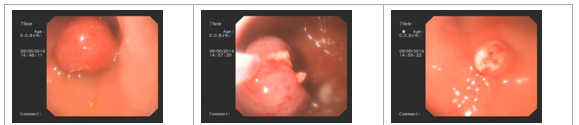

張**,男,74歲,因腹痛半年余來我院消化內(nèi)科門診就診,入院后行電子結(jié)腸鏡檢查,直腸可見息肉3個(gè),直徑0.7×0.6-0.8×0.9CM,帶蒂,表面充血水腫,經(jīng)腸道準(zhǔn)備后在內(nèi)鏡下行息肉電凝術(shù)及電切術(shù),手術(shù)順利,術(shù)中見少量出血,給予內(nèi)鏡下止血治療,術(shù)后安全返回病房,恢復(fù)良好。

高**,男,53歲,因腹痛10余天入院,入院后行電子胃鏡檢查,顯示胃體大彎側(cè)可見一2×2cm的息肉,表面光滑,在內(nèi)鏡下行息肉電凝術(shù)及電切術(shù),手術(shù)順利,術(shù)中無明顯出血,術(shù)后恢復(fù)良好。